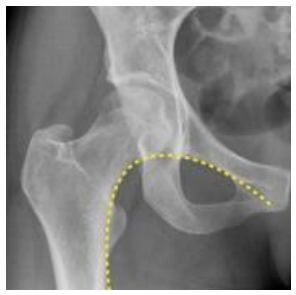

Qual o nome da linha traçada na radiografia abaixo?